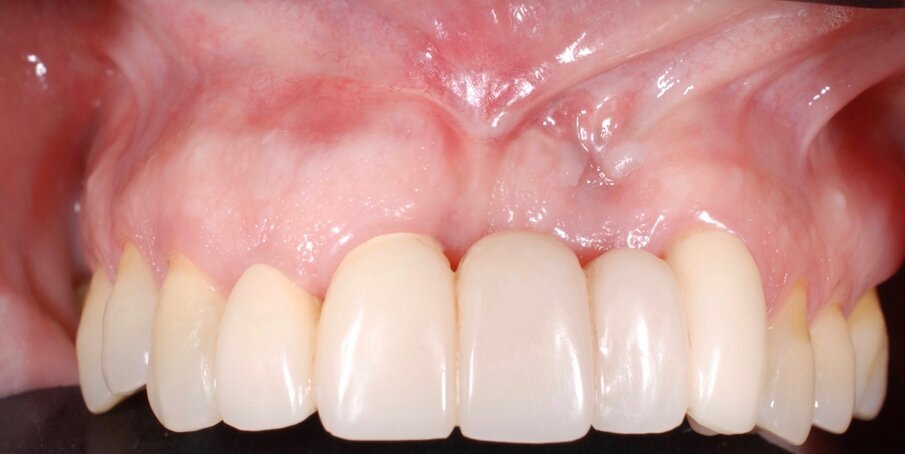

In questo articolo presentiamo un caso clinico che dimostra come il posizionamento improprio di un impianto può rendere impossibile la riabilitazione protesica, che richiede una nuova pianificazione chirurgica e riabilitativa per ottenere l’estetica desiderata. La paziente si presenta alla nostra osservazione con una riabilitazione protesica incongrua, con flangia in resina, a supporto dentale ed implantare, con la presenza di un impianto in posizione 2.1 vestibolarizzato e con l’emergenza nel fornice, in mucosa alveolare. Dalla valutazione della Tac si evince la posizione errata dell’impianto e la perdita consistente in senso trasversale della compagine ossea (Figg. 1, 2). Pertanto si opta per il seguente piano di trattamento che prevede: rimozione dell’impianto e preparazione protesica dell’elemento 2.3, confezionamento di un primo provvisorio a supporto dentale che servirà a guidare la guarigione dei tessuti (Figg. 3-7). A distanza di 4 mesi si procede a un innesto epitelio connettivale libero con prelievo dal palato per compensare il gap dei tessuti molli in senso trasversale, quindi viene ribasato il provvisorio in modo tale da favorire la guarigione dei tessuti (Figg. 8-11). A 9 mesi dalla maturazione dei tessuti si procede alla finalizzazione protesica fissa a supporto dentale (Figg. 12-14).

Fig. 12 - Guarigione a 9 mesi.

Fig. 14 - Finalizzazione protesica.

Indipendentemente dalla causa, quando un impianto non è ben posizionato, la riabilitazione protesica potrebbe non essere adeguata dal punto di vista meccanico, funzionale ed estetico. Nel caso qui presentato, era necessaria la rimozione dell’impianto e una nuova pianificazione chirurgica e protesica. Nonostante i limiti estetici della riabilitazione protesica iniziale, considerando che non è stato eseguito alcun innesto di tessuto osseo, senza reinserire l’impianto, ma gestendo adeguatamente i tessuti molli si è riusciti ad ottenere un risultato estetico valido e predicibile nel tempo.